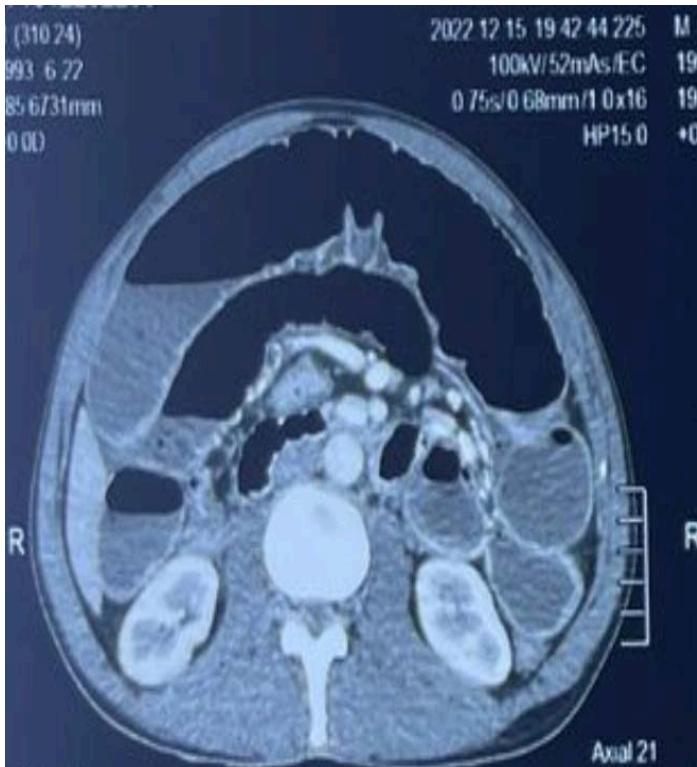

Abdominal CT scan showed small and large bowel distention with a caliber disparity in the right iliac fossa and air-fluid levels.

Figure 2: Air-fluid levels